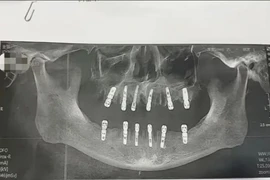

Một người đàn ông lớn tuổi đã tử vong 13 ngày sau khi nhổ 23 chiếc răng và khoan 12 lỗ vào xương hàm để trồng răng mới trong cùng một ngày tại phòng khám nha khoa ở Trung Quốc.